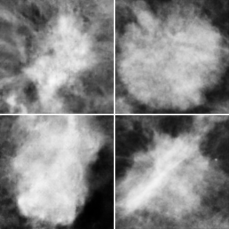

Fig. 2(a) shows two synthetic masses (left column) and two real masses (right column) depicting that DCGAN could generate visually-similar masses to the ones it was trained on. Moreover, Fig. 2(b) shows the F1 score for different training sizes, where each line represents one augmentation approach. The blue line (ORG) shows the classification results using the original unbalanced training dataset. As more training images are available, the classifier increases its performance until k=750 where the performance saturates. When comparing the blue and the green lines (GAN), the latter shows faster improvements which shows that the generator has learned to unlock unseen images in the real distribution helping the classifier to distinguish masses among normal tissue. If, on the other hand, the original data is augmented using horizontal and vertical flipping (the orange line of Aug ORG), the classifier performs similarly to GAN (green) at medium sizes. Finally, the red line (Aug GAN) shows the F1 score when random online flipping was applied on the combined real and synthetically-generated images. As can be depicted in the figure, Aug GAN outperformed all other modes at any k, except a negligible drop at 1,300, with the maximum improvement at 250 with about 0.09 over ORG approach.

Figure 2: (a) Synthetic (left column) and real (right column) breast mass lesions. (b) F1 score as a function of the size of the positive training set investigating four approaches: ORG, GAN, Aug ORG, and Aug GAN.